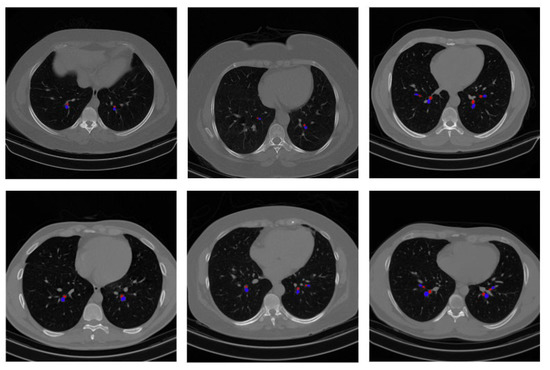

- To identify BA pairs, lung segmentation and image cleaning are conducted using several image preprocessing and custom-developed algorithms.

- Potential bronchi and arteries are identified by applying several algorithms based on their characteristics, and the BA pairs are extracted by matching the coordinates of potential bronchi and arteries.

- The BA ratio of the detected BA pares is determined in an automated approach, and the results are evaluated and validated based on human assessment and deep learning-based techniques.